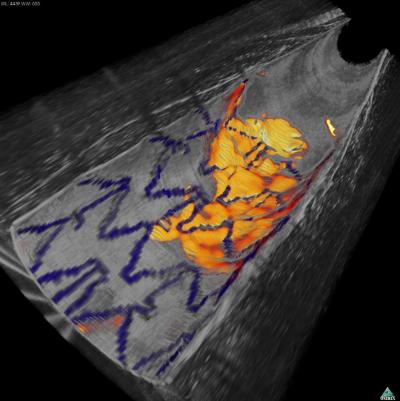

A new device that combines two microimaging technologies can reveal both the detailed anatomy of arterial linings and biological activities that, in coronary arteries, could indicate the risk of heart attacks or the formation of clots in arterial stents. In their report receiving early online release in Nature Medicine, Massachusetts General Hospital (MGH) investigators describe using an intra-arterial catheter combining both optical frequency-domain imaging (OFDI) and near-infrared fluorescence (NIRF) imaging to obtain simultaneous structural and molecular images of internal arterial surfaces in rabbits.

Developed at the Wellman Center, OFDI utilizes a fiberoptic probe with a constantly rotating laser tip to create detailed molecular images of interior surfaces such as arterial walls. While OFDI can be used to guide procedures like coronary artery angioplasty and to confirm the correct positioning of metal stents inserted to keep cleared arteries open, its ability to determine important details of stent healing is limited. Properly healed stents become covered with endothelium, the same tissue that normally coats the arterial surface; but stents can become coated with the clot-inducing protein fibrin, which may put patients at risk for stent thrombosis – a clot that blocks bloodflow through the stent – and OFDI cannot determine the molecular composition of tissue covering a stent.

Intravascular NIRF technology was developed in the MGH Cardiovascular Research Center (CVRC), in collaboration with colleagues at the Technical University of Munich, and uses special imaging agents to detect cells and molecules involved in vascular processes like clotting and inflammation. Recognizing the potential advantage of combining both technologies, the Wellman researchers worked with the MGH-CVRC team, led by Farouc Jaffer, MD, PhD, of the MGH Heart Center to develop an integrated OFDI-NIRF imaging system incorporated in the same intravascular probe used for OFDI alone.

The team first confirmed that the system could provide detailed structural images of a stent implanted in a cadaveric human coronary artery and could accurately identify the presence of fibrin on the stent. In a series of experiments in living rabbits, the OFDI-NIRF system was able to detect fibrin on implanted stents – including areas where it was not detected by OFDI alone – and to identify the presence of both atherosclerotic plaques and enzymatic activity associated with inflammation and plaque rupture. The enzyme signal detected by NIRF was not uniform throughout the imaged plaques, indicating biological differences that could be relevant to prognosis and treatment planning.